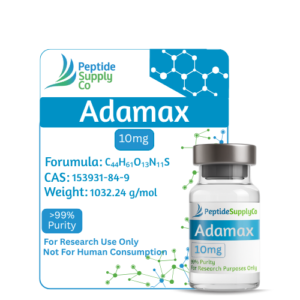

Featured Products

-

-

-